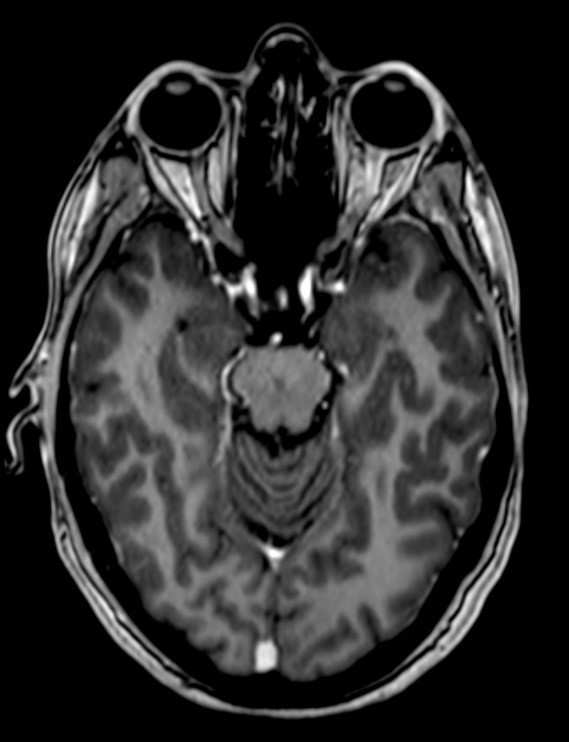

Dissémination spatiale : plusieurs territoires atteints cliniquement, au moins deux territoires atteints en IRM parmi : le territoire périventriculaire, le trajet des nerfs optiques, la région sous/juxta- et intracorticale, la fosse postérieure, la moelle épinière. Particularité des nouveaux critères : prendre en compte les lésions de la fosse postérieure et de la moelle symptomatiques.

Dissémination temporelle : plusieurs poussées cliniques dans le temps, apparition de nouvelles lésions entre les IRM, ou certaines lésions prennent le contraste et pas d’autres sur une même IRM, ou apparition d’une synthèse intrathécale dans le LCS.